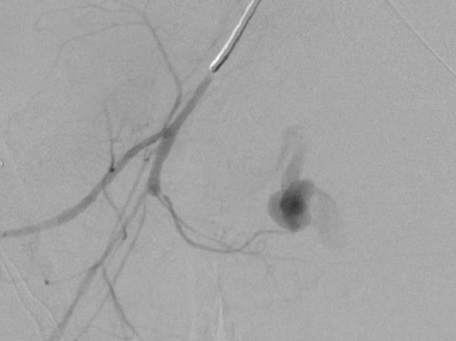

医源性肾创伤,移植肾活检后,动脉瘤

![]()

产后出血子宫动脉微Coil末端栓塞:导管头尽量接近出血点

直接栓塞/终末动脉栓塞/产后大出血栓塞

男,30,输尿管近端结石,体外碎石后,大量血尿